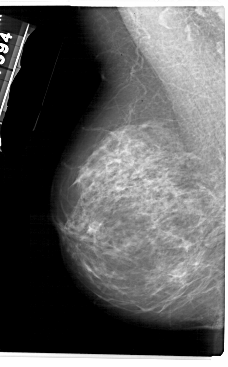

ics_version 1.0 filename A-1944-1 DATE_OF_STUDY 19 7 1994 PATIENT_AGE 72 FILM FILM_TYPE REGULAR DENSITY 3 DATE_DIGITIZED 8 7 1999 DIGITIZER HOWTEK 43.5 SEQUENCE LEFT_CC LINES 5431 PIXELS_PER_LINE 3106 BITS_PER_PIXEL 12 RESOLUTION 43.5 NON_OVERLAY LEFT_MLO LINES 5491 PIXELS_PER_LINE 3406 BITS_PER_PIXEL 12 RESOLUTION 43.5 NON_OVERLAY RIGHT_CC LINES 5116 PIXELS_PER_LINE 3046 BITS_PER_PIXEL 12 RESOLUTION 43.5 OVERLAY RIGHT_MLO LINES 5491 PIXELS_PER_LINE 3391 BITS_PER_PIXEL 12 RESOLUTION 43.5 OVERLAY |